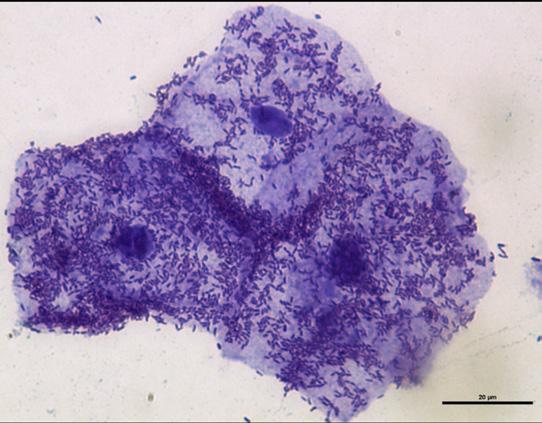

Figure 4. Micrograph showing uroepithelial cells shed from a patient with a UTI. Notice the large number of adherent bacteria found on the bladder cells. Shedding of epithelial cells is a powerful mechanism to reduce bacterial load in the bladder.